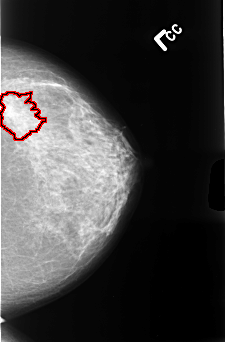

FILE: B_3477_1.LEFT_CC.OVERLAY

TOTAL_ABNORMALITIES 1

ABNORMALITY 1

LESION_TYPE MASS SHAPE IRREGULAR-ARCHITECTURAL_DISTORTION MARGINS ILL_DEFINED-SPICULATED

ASSESSMENT 4

SUBTLETY 4

PATHOLOGY MALIGNANT

TOTAL_OUTLINES 1

BOUNDARY